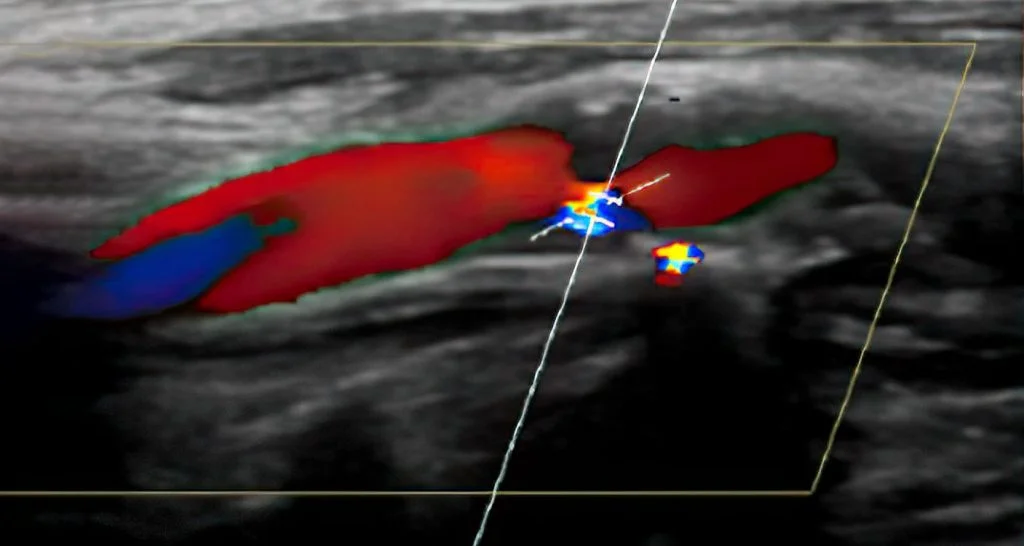

• Extrakranielle Farbduplex- und Dopplersonographie

Farbduplex-Sonographie eines hirnzuführenden Gefäßes, eine Verengung ist gut sichtbar.